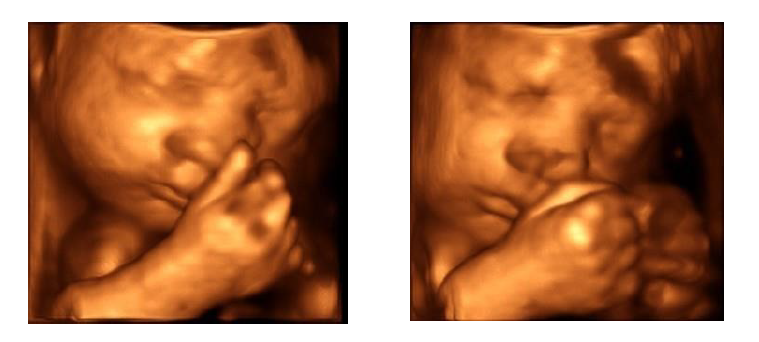

Fotografie 3D zobrazení plodu

Cena je 900 Kč (u vícečetného těhotenství 1200 Kč). V ceně je flash disk s obrázky, tisk 2 fotografií ve formátu A4. Objednat se lze během dopoledne na čísle 466 015 533. Ideální doba pro takovéto zobrazení plodu je mezi 24. a 28. týdnem těhotenství. Je třeba ale zdůraznit, že kvalita zobrazení závisí na hmotnosti pacientky, uložení plodu v děloze a na množství plodové vody. Aktuální ceník najdete zde.